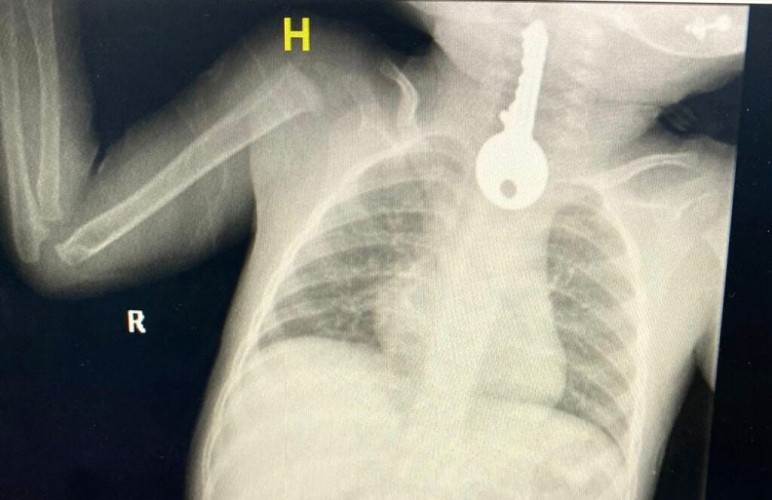

وبين مجمع الملك فيصل الطبي أنهم استقبلوا حالة طفل في وضع صحي حرج يعاني من ضيق في التنفس مما استدعى إلى تقديم الإسعافات الأولية وإجراء الفحوصات السريرية والإشعاعية التي كشفت وجود جسم غريب على شكل مفتاح في المريء.

وقال الفريق المعالج للحالة أنه تم على الفور عمل منظار عاجل واستخراج مفتاح حديدي من المريء كاد أن يودي بحياته ثم متابعته في قسم التنويم من قبل الفرق التمريضية حتى استقرت الحالة وخرج بالسلامة ولله الحمد.